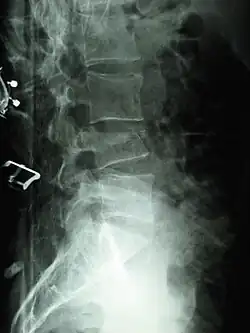

Compression fractures are usually diagnosed on spinal radiographs, where a wedge-shaped vertebra may be visible or there may be loss of height of the vertebra. In addition, bone density measurement may be performed to evaluate for osteoporosis. When a tumor is suspected as the underlying cause, or the fracture was caused by severe trauma, CT or MRI scans may be performed.

X-ray of the lumbar spine with a compression fracture of the third lumbar vertebra. -